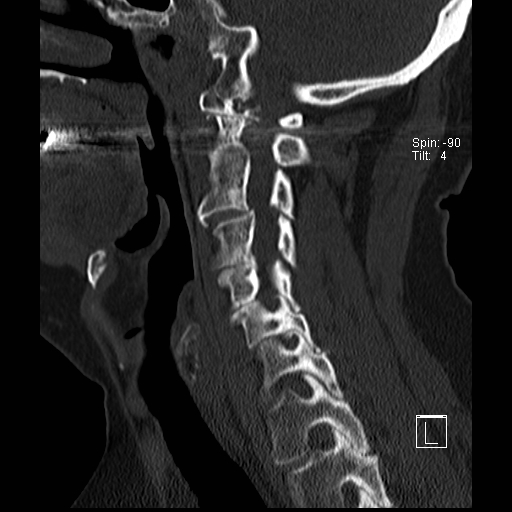

Trật khớp đội – trục

Cột sống cổ thường bị ảnh hưởng trong viêm khớp dạng thấp và có thể biểu hiện dưới dạng mất vững khớp đội – trục, trật khớp dưới trục hoặc lồng nền sọ kèm theo sụt lún sọ não.

Sụt lún sọ não xảy ra khi mỏm răng xâm lấn vào lỗ chẩm.

Trật khớp đội – trục là một biến chứng quan trọng và có thể đe dọa tính mạng của viêm khớp dạng thấp. Tình trạng này được xác định khi khoảng cách giữa mỏm răng C2 và cung đốt đội vượt quá 3 mm. Nguyên nhân là do lỏng lẻo dây chằng do viêm.

Mất vững tại khớp này có thể gây ra nhiều triệu chứng thần kinh do chèn ép tủy sống.

Hình ảnh

Khi cúi cổ, khoảng cách giữa mỏm răng và mặt sau cung trước đốt đội bị giãn rộng (14 mm) (bình thường ≤3 mm).